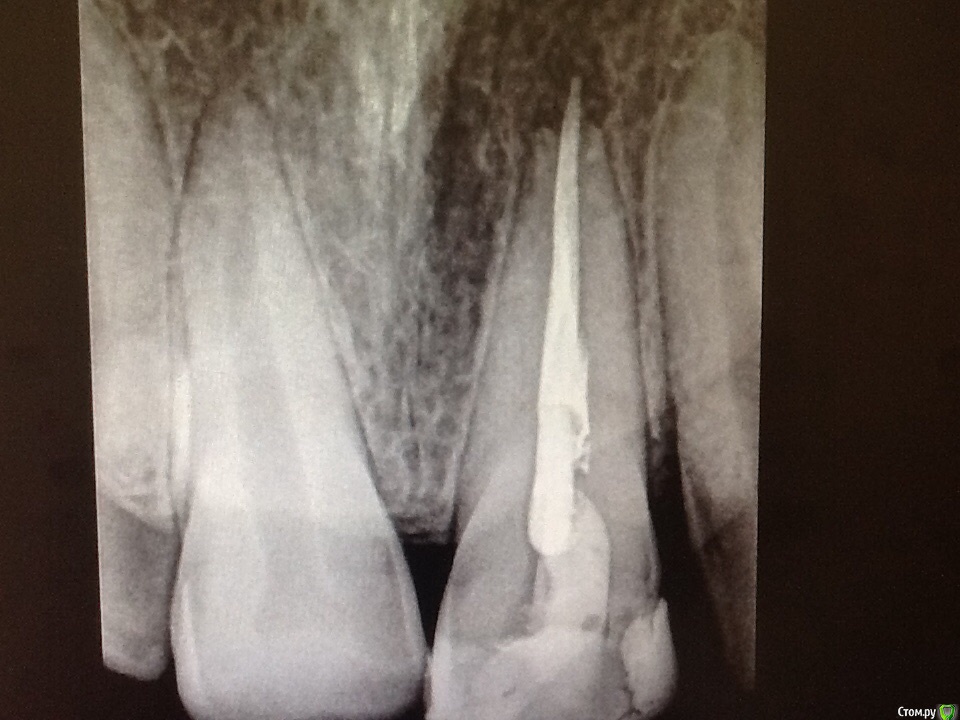

Мартовский Опубликовано 29 мая, 2015 Поделиться Опубликовано 29 мая, 2015 Канал обработать, в апекс прорут, потом к хирургу. Не надо никаких резекций с ретроградками, просто пусть почистит и все. Пример здесьhttp://forum.stom.ru/topic/28486-rekoll-22-ochen-khotel-zhit/ 3 Ссылка на комментарий

Ico Опубликовано 29 мая, 2015 Поделиться Опубликовано 29 мая, 2015 Канал обработать, в апекс прорут, потом к хирургу. Не надо никаких резекций с ретроградками, просто пусть почистит и все. Пример здесьhttp://forum.stom.ru/topic/28486-rekoll-22-ochen-khotel-zhit/А рубцы на десне и последующая рецессия в эстетически значимой зоне Вас не смущают? imho если и резать,то исключить распространение резорбции,чтобы не резать потом повторно.Исключением можно сделать,если хирург работает в скопе с соответствующими инструментами и шовным от 7ки. Ссылка на комментарий

сирена Опубликовано 29 мая, 2015 Поделиться Опубликовано 29 мая, 2015 (изменено) Видимо мы по разному на нее смотрим хотя если нет претензий к эстетике можно и викрилом 4 кой. Мощно )) Ну,тут полноценная резекция с ретроградной пломбировкой,а мы говорим просто о ревизии,очаг-то мизерный.Я бы разрез примерно так сделала в этом случае,только ещё меньше.Но,конечно,нитки потоньше и увеличение желательны)Сейчас,блин,забыла,как видео вставлятьhttp://www.youtube.com/watch?v=QSfS24zb01Y Изменено 29 мая, 2015 пользователем сирена 1 Ссылка на комментарий

M@estro Опубликовано 29 мая, 2015 Поделиться Опубликовано 29 мая, 2015 Канал обработать, в апекс прорут, потом к хирургу. Не надо никаких резекций с ретроградками, просто пусть почистит и все. Пример здесьhttp://forum.stom.ru/topic/28486-rekoll-22-ochen-khotel-zhit/ Технически - это ретроградная ревизия, т.е. не все через канал. Ссылка на комментарий